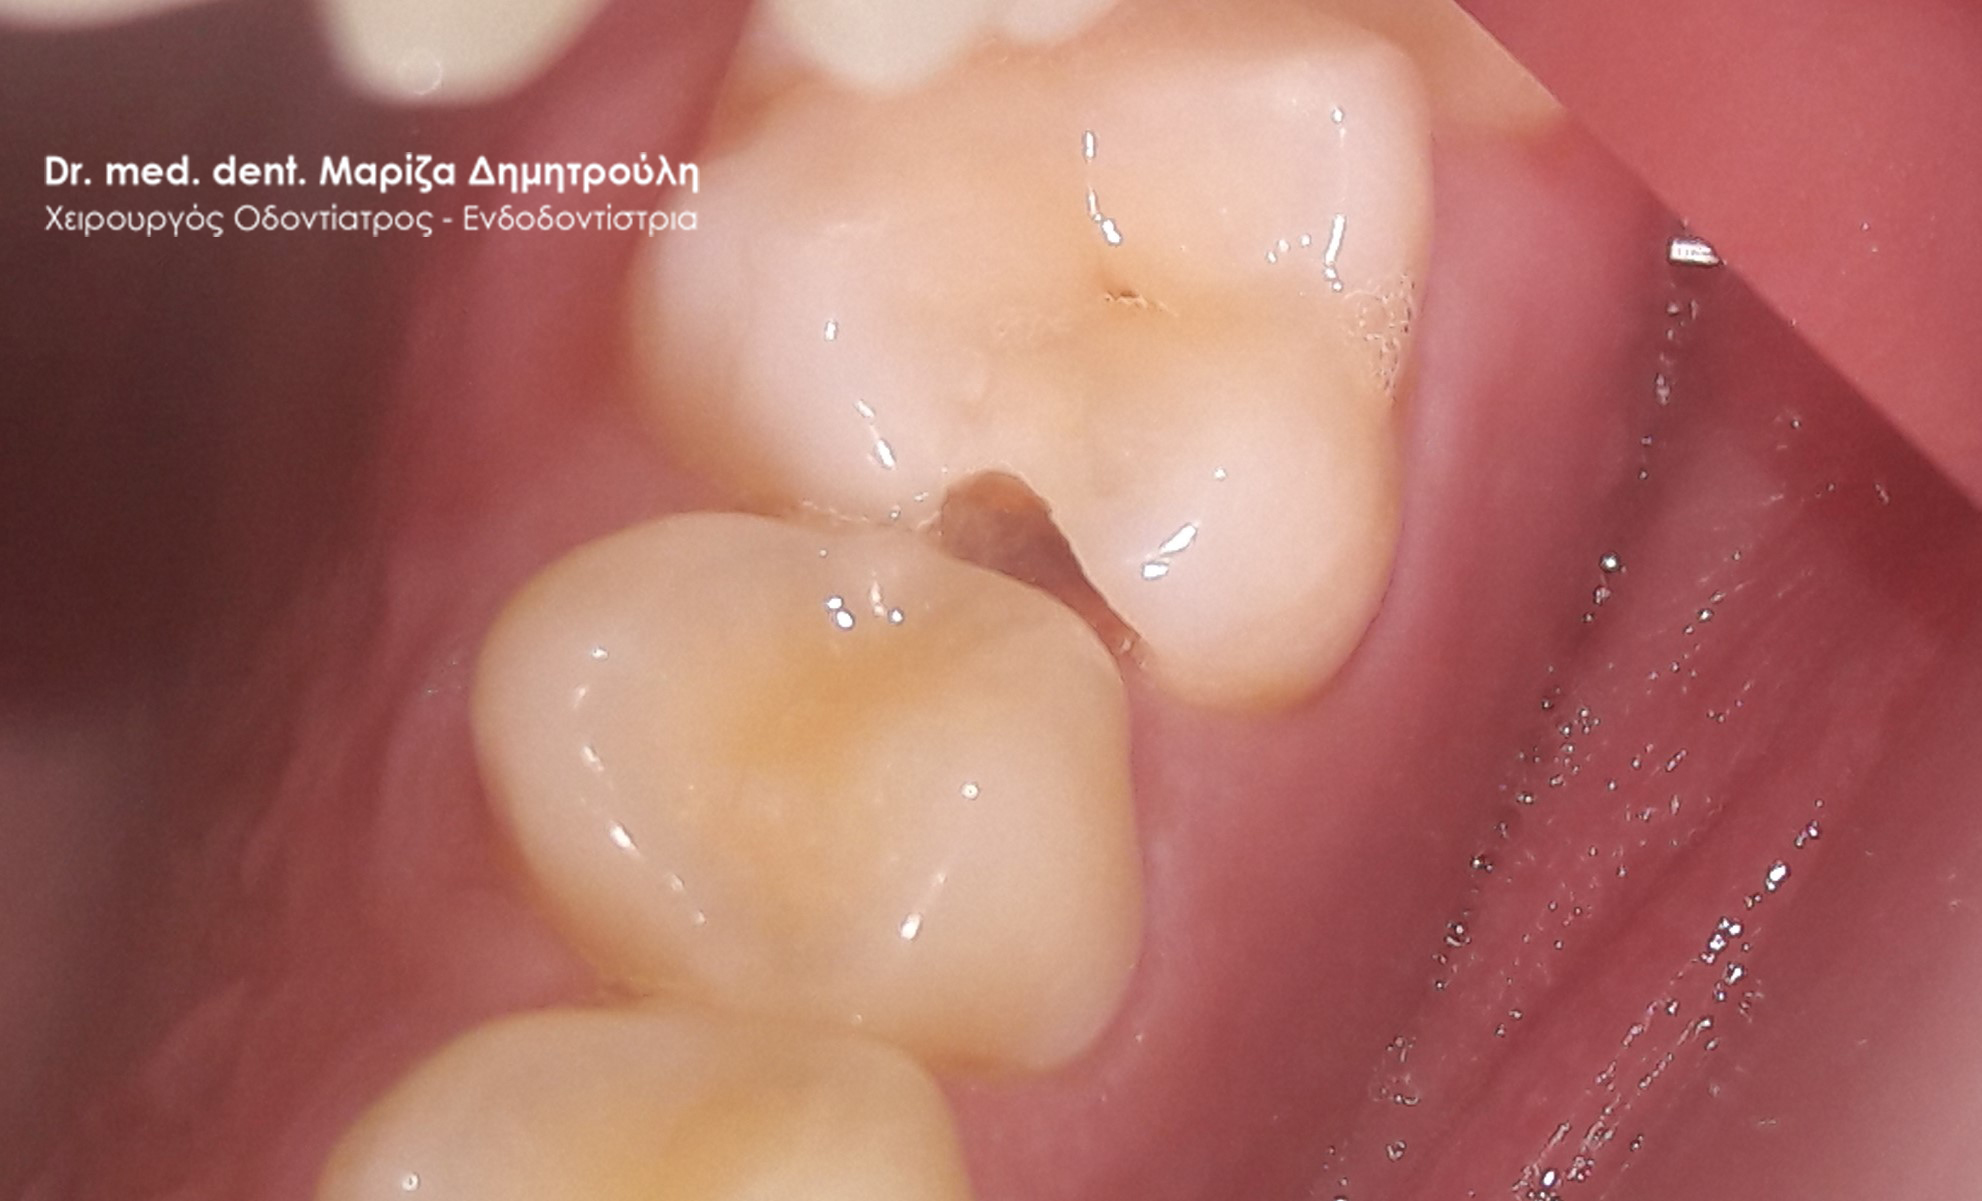

Ο ασθενής επιθυμούσε την αντικατάσταση των μαύρων σφραγισμάτων αμαλγάματος στον πρώτο δεξιό γομφίο και στο δεύτερο γομφίο με λευκά σφραγίσματα σύνθετης ρητίνης. Η θεραπεία πραγματοποιήθηκε με τη χρήση ελαστικού απομονωτήρα, όπως ορίζουν τα παγκόσμια πρωτόκολλα οδοντιατρικής για την αφαίρεση των μαύρων σφραγισμάτων. Όταν οι οδοντίατροι χρησιμοποιούν απομονωτήτρα κατά την αφαίρεση σφραγισμάτων αμαλγάματος, τότε ο ασθενής εισπνέει ελάχιστα και δεν καταπίνει τον υδράργυρο, που απελευθερώνεται κατά τη διαδικασία αυτή.

ΠΡΙΝ

META